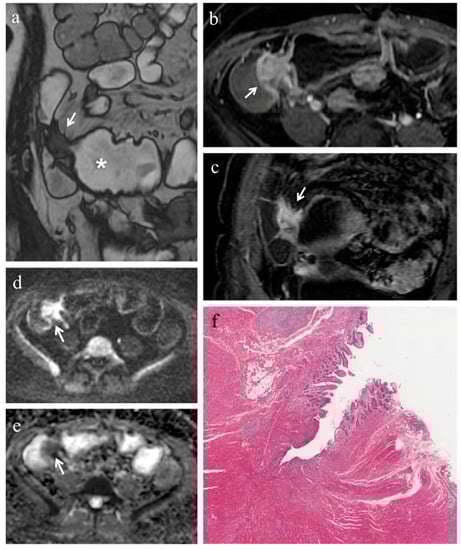

Figure 2. (af). MRE in a 19-year-old man with CD: stenosis of the terminal ileum with concomitant inflammation and fibrosis. (a) Coronal T2-weighted image and (b) axial FIESTA image show marked wall thickening of the terminal ileum with luminal narrowing (white arrows). On (c) axial contrast-enhanced fat-suppressed T1-weighted image, the mural thickening of the terminal ileum displays intense mucosal enhancement (white arrow). The same intestinal segment demonstrates high signal intensity on (d) the DW image (b = 800 s/mm2) and low signal intensity on (e) the corresponding ADC map (white arrows) (mean ADC value 1.096 × 10−3 mm2/s), a finding consistent with restricted diffusion. (f) Histopathological section from the ileal stricture: hematoxylin and eosin-stained sample (H&E 10×). CD exhibiting mild/moderate fibrosis (FS = 1) and severe inflammation (AIS = 10): mucosal ulceration and severe inflammatory infiltration on the top; mild/moderate fibrosis, edema and inflammatory infiltration in submucosal layer on the bottom.

In 18 (78.3%) ileal segments, inflammation and fibrosis coexisted (Figure 1 and Figure 2), in 5 (21.7%) cases inflammatory alterations without fibrosis were found (Figure 3), whereas under no circumstances was fibrosis without inflammation encountered. No significant correlation was highlighted between AIS and FS (p = 0.22).

Pattern of enhancement. The diseased bowel wall showed the following enhancement patterns: homogeneous in 6 cases (26.1%) (Figure 1b,c, Figure 3b), mucosal in 8 cases (34.8%) (Figure 2c) and layered in 9 cases (39.1%). Pattern of enhancement did not show significant variations according to AIS (p = 0.56) or FS (p = 0.49).

Pre-stenotic luminal diameter. Maximum caliber of pre-stenotic upstream bowel (mean 33 ± 14 mm, range 17–80 mm) did not correlate with inflammation score (p = 0.50). On the other hand, pre-stenotic bowel dilatation positively correlated with the fibrosis score (p = 0.002): upstream bowel dilatation increased according to fibrosis grade (Figure 1a). In particular, pre-stenotic luminal diameter was higher in patients with severe fibrosis than in those with none or mild/moderate fibrosis (p < 0.05) (Figure 4, Panel a). The mean pre-stenotic luminal diameters were 25 ± 4 mm, 27 ± 5 mm and 47 ± 18 mm for none, mild/moderate and severe FS, respectively. Moreover, this measurement showed a high accuracy (AUC 0.75, p < 0.001) for discriminating between none and mild/moderate–severe bowel wall fibrosis; using a threshold value of 30 mm, the sensitivity and specificity were 100% and 44%, respectively (Figure 5, Panel a).

3.4. Analysis of DWI Quantitative Measures (ADC)

The mean size of the ROIs used to measure the ADC value in the diseased bowel wall was 48 ± 22 mm2. The overall mean of ADC values was 1.168 ± 0.181 × 10−3 mm2/s (range 0.745–1.473 × 10−3 mm2/s). No significant correlation was found between ADC and inflammation score (p = 0.41). The ADC value was negatively correlated with the fibrosis score (p < 0.001). The ADC value was different between FS grades (p < 0.05) (Figure 4, Panel b). The means of the ADC values were 1.371 × 10−3 mm2/s for none, 1.224 × 10−3 mm2/s for mild/moderate and 0.936 × 10−3 mm2/s for severe FS. ADC values showed a high accuracy (AUC 0.97, p < 0.001) for discriminating between none and mild/moderate–severe bowel wall fibrosis. Using a threshold ADC value of 1.300 × 10−3 mm2/s, the sensitivity and specificity were 80% and 100%, respectively (Figure 5, Panel b). Qualitative and quantitative MRE findings are summarized in Table 3.